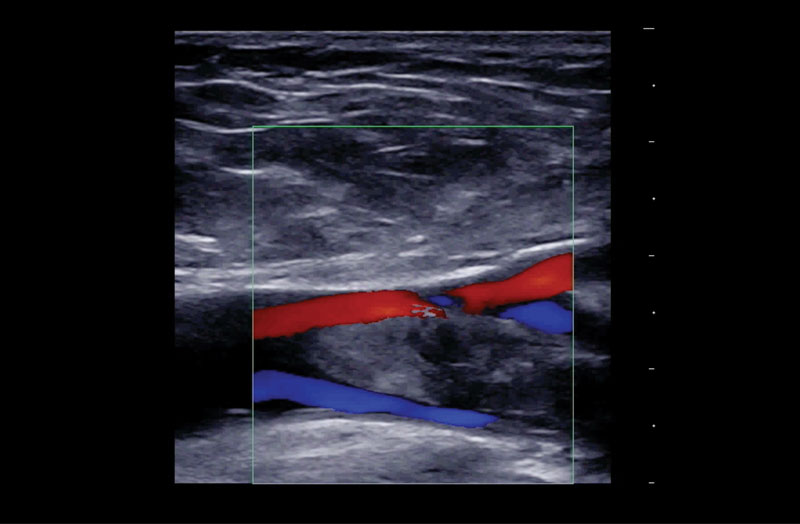

The Z.One PRO Ultrasound System Emerald Edition 2.0 is a powerful and portable advanced point-of-care imaging platform. Powered by software-based ZONE Sonography® Technology+ (ZST+), the Z.One PRO System provides optimal B-mode and Doppler imaging for patients, regardless of body habitus, helping ensure a reliable diagnosis. With a full family of transducers (from 2 – 20 MHz) and a wide range of applications, the Z.One PRO System is the imaging answer to your difficult clinical cases.

Advanced needle visualization technology allows increased needle visibility even during steep-angled procedures, while maintaining superior image quality. Improved confirmation of needle location in tissue minimizes harm to surrounding tissue.